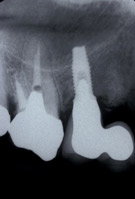

レントゲンで見ると根の先に大きな病気(根尖病変)があり、また歯自体も割れてしまっています。

| レントゲン像です。 大きな根の病気ができています |

ソケットリフトもおこないました。 |